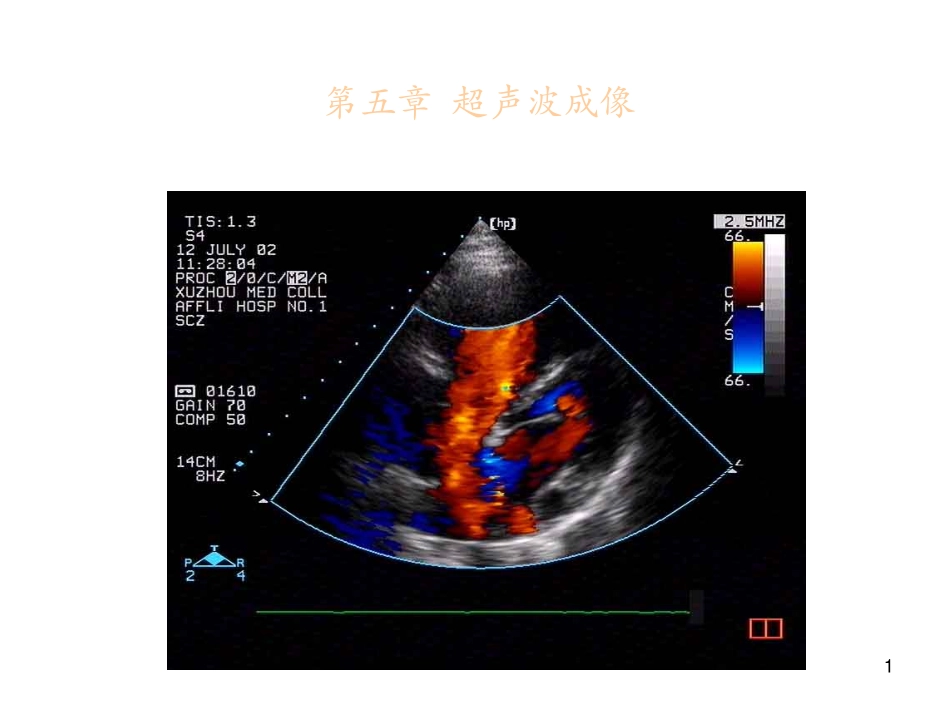

1第五章超声波成像2第二章超声波成像•主要内容•2.1超声波的物理性质•2.2超声探测的物理基础•2.3超声成像系统工作原理•2.4超声多普勒成像系统*3第一节超声波的物理性质45.1.1超声的基本概念•1.超声:指超过人耳听觉范围(20Hz~20kHz)。频率>20kHz的声波叫做超声波。•2.超声波:属于声波范畴,具有声的共同物理性质。如:必须通过弹性介质进行传播,传播方式为纵波(疏密波),具有反射、折射、绕射,以及在不同介质中(空气、水、软组织、骨骼)中具有不同的声速和不同的衰减等。•3.超声频率:诊断最常用的超声频率是1M~40MHz。55.1.1超声的基本概念•4.超声波特点•(1)直线传播且易会聚:频率高,波长短,直线传播,具有较强的穿透能力,能量容易会聚。•(2)容易电声转换且能量大:使介质的微粒振动,虽然振幅很小,但加速度非常大,具有很大的能量,能量和频率f2成正比。•(3)物理机制复杂且参数多:在产生、传播、接收与相互作用、能量转换等过程中,其物理机制复杂、相互影响的因素多。65.1.1超声的基本概念•(4)超声工作安静且危害少:超声工作时人耳听不到,环境安静。在影像学诊断工作中,小剂量超声波对人体无危险性。•超声成像是以人体解剖学、病理学等形态学为基础,依靠超声的各种成像技术来获取人体器官及组织的断面解剖图像。75.1.2超声的基本物理量•基本物理量:频率(f)、波长(λ)、声速(c)。•三者关系:f=c/λ•λ与f成反比,f愈高,λ愈短。•(一)声速•不同f的超声在相同的介质中传播时,声速c基本相同;•同一f的超声波在不同的介质中传播时,c是不同的。85.1.2超声的基本物理量•在不同的介质中,c有很大的差别:–空气(20℃)344m/s–脂肪1476m/s–水(37℃)1524m/s–肝脏1570m/s–颅骨3360m/s•超声在人体组织中的传播速度是超声诊断设备测量病变组织位置和大小的依据。•人体软组织的声速平均为1500m/s左右,与水的声速相近。骨骼的声速最高,相当于软组织的2倍以上。95.1.2超声的基本物理量•(二)周期和频率•周期T:介质中的质点在平衡位置往返摆动一次(传播一个波长)所需要的时间,单位为s。•频率f:质点在1s时间内完成振动的次数(弹性介质中任一给定点在单位时间内所通过的波数),即单位时间内声源振动的次数,单位Hz。•105.1.2超声的基本物理量•f由波源的机械振动所决定,与声波传播的介质无关。•T与f互为倒数:T=1/f•超声诊断仪采用不同的频率,主要根据受检脏器或组织的深度和病灶的大小来选择,常用的f在1MHz~15MHz之间,最常用的是1MHz、3MHz、3.5MHz、5MHz、7.5MHz。115.1.2超声的基本物理量•(三)波长•波长λ:超声在一个周期内传播的距离(波上任意两个相邻的同相位点之间的距离),单位m。对于纵波,等于两相邻密集点(或稀疏点)间的距离;对于横波,则是从一个波峰(或波谷)到相邻波峰(或波谷)的距离。•λ决定了成像的纵向极限分辨力,在纵向上需检出的病灶必须大于半个波长时,才能被正确分辨;•f决定可成像的组织深度,f越高可检出深度越浅。125.1.2超声的基本物理量•(四)声压•声波作为纵波在弹性介质中传播时,介质各部分时而密集时而稀疏,介质各部分的压强相应变化。•没有声波传播时,介质某处的静压强P0,该处形成密部的瞬间,压强P高于P0;该处形成疏部的瞬间,压强P低于P0。•声压:声波在介质中传播产生的瞬时压强值P与P0的比值,单位是Pa。135.1.2超声的基本物理量•声压是变化的,若声源作周期振动,声压也随着周期性变化。声压的大小用幅值Pm表示。声压幅值Pm与c、介质密度ρ、声波的振幅A和角频率ω有关:•Pm=Aωρc145.1.2超声的基本物理量•(五)声强•声强:超声在传播过程中,垂直于超声传播方向上单位面积在单位时间内通过的超声能量,用W/m2来度量。是表示超声传播过程中声能强弱的物理量:••在同一介质中,密度ρ和c不变,声强主要与•f2、质点振幅A2成正比。•声压与声强关系:••ρ和c不变,声强与Pm2成正比。2222IfAcπρ=2/2mIPcρ=155.1.2超声的基本物理量•(六)声阻抗•声阻抗(特性阻抗):对于各向同性的均匀介质中的声波,介质中某点声...